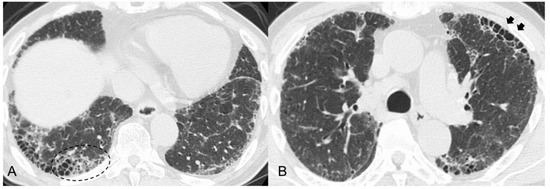

- Suzuki, A.; Sakamoto, S.; Kurosaki, A.; Kurihara, Y.; Satoh, K.; Usui, Y.; Nanki, T.; Arimura, Y.; Makino, H.; Okada, Y.; et al. Chest high-resolution CT findings of microscopic polyangiitis: A Japanese first nationwide prospective cohort study. AJR Am. J. Roentgenol. 2019, 213, 104–114. [Google Scholar] [CrossRef]

- Yamakawa, H.; Sato, S.; Nakamura, T.; Nishizawa, T.; Kawabe, R.; Oba, T.; Horikoshi, M.; Akasaka, K.; Amano, M.; Kuwano, K.; et al. Prognostic value of radiological findings indeterminate for UIP pattern and anterior upper lobe honeycomb-like lesion in chronic fibrosing interstitial lung disease associated with MPO-ANCA. BMC Pulm. Med. 2021, 21, 346. [Google Scholar] [CrossRef] [PubMed]

- Sun, X.; Peng, M.; Zhang, T.; Li, Z.; Song, L.; Li, M.; Shi, J. Clinical features and long-term outcomes of interstitial lung disease with anti-neutrophil cytoplasmic antibody. BMC Pulm. Med. 2021, 21, 88. [Google Scholar] [CrossRef] [PubMed]

| Increased attenuation around honeycombing and traction bronchiectasis (19–39%) | ― | |